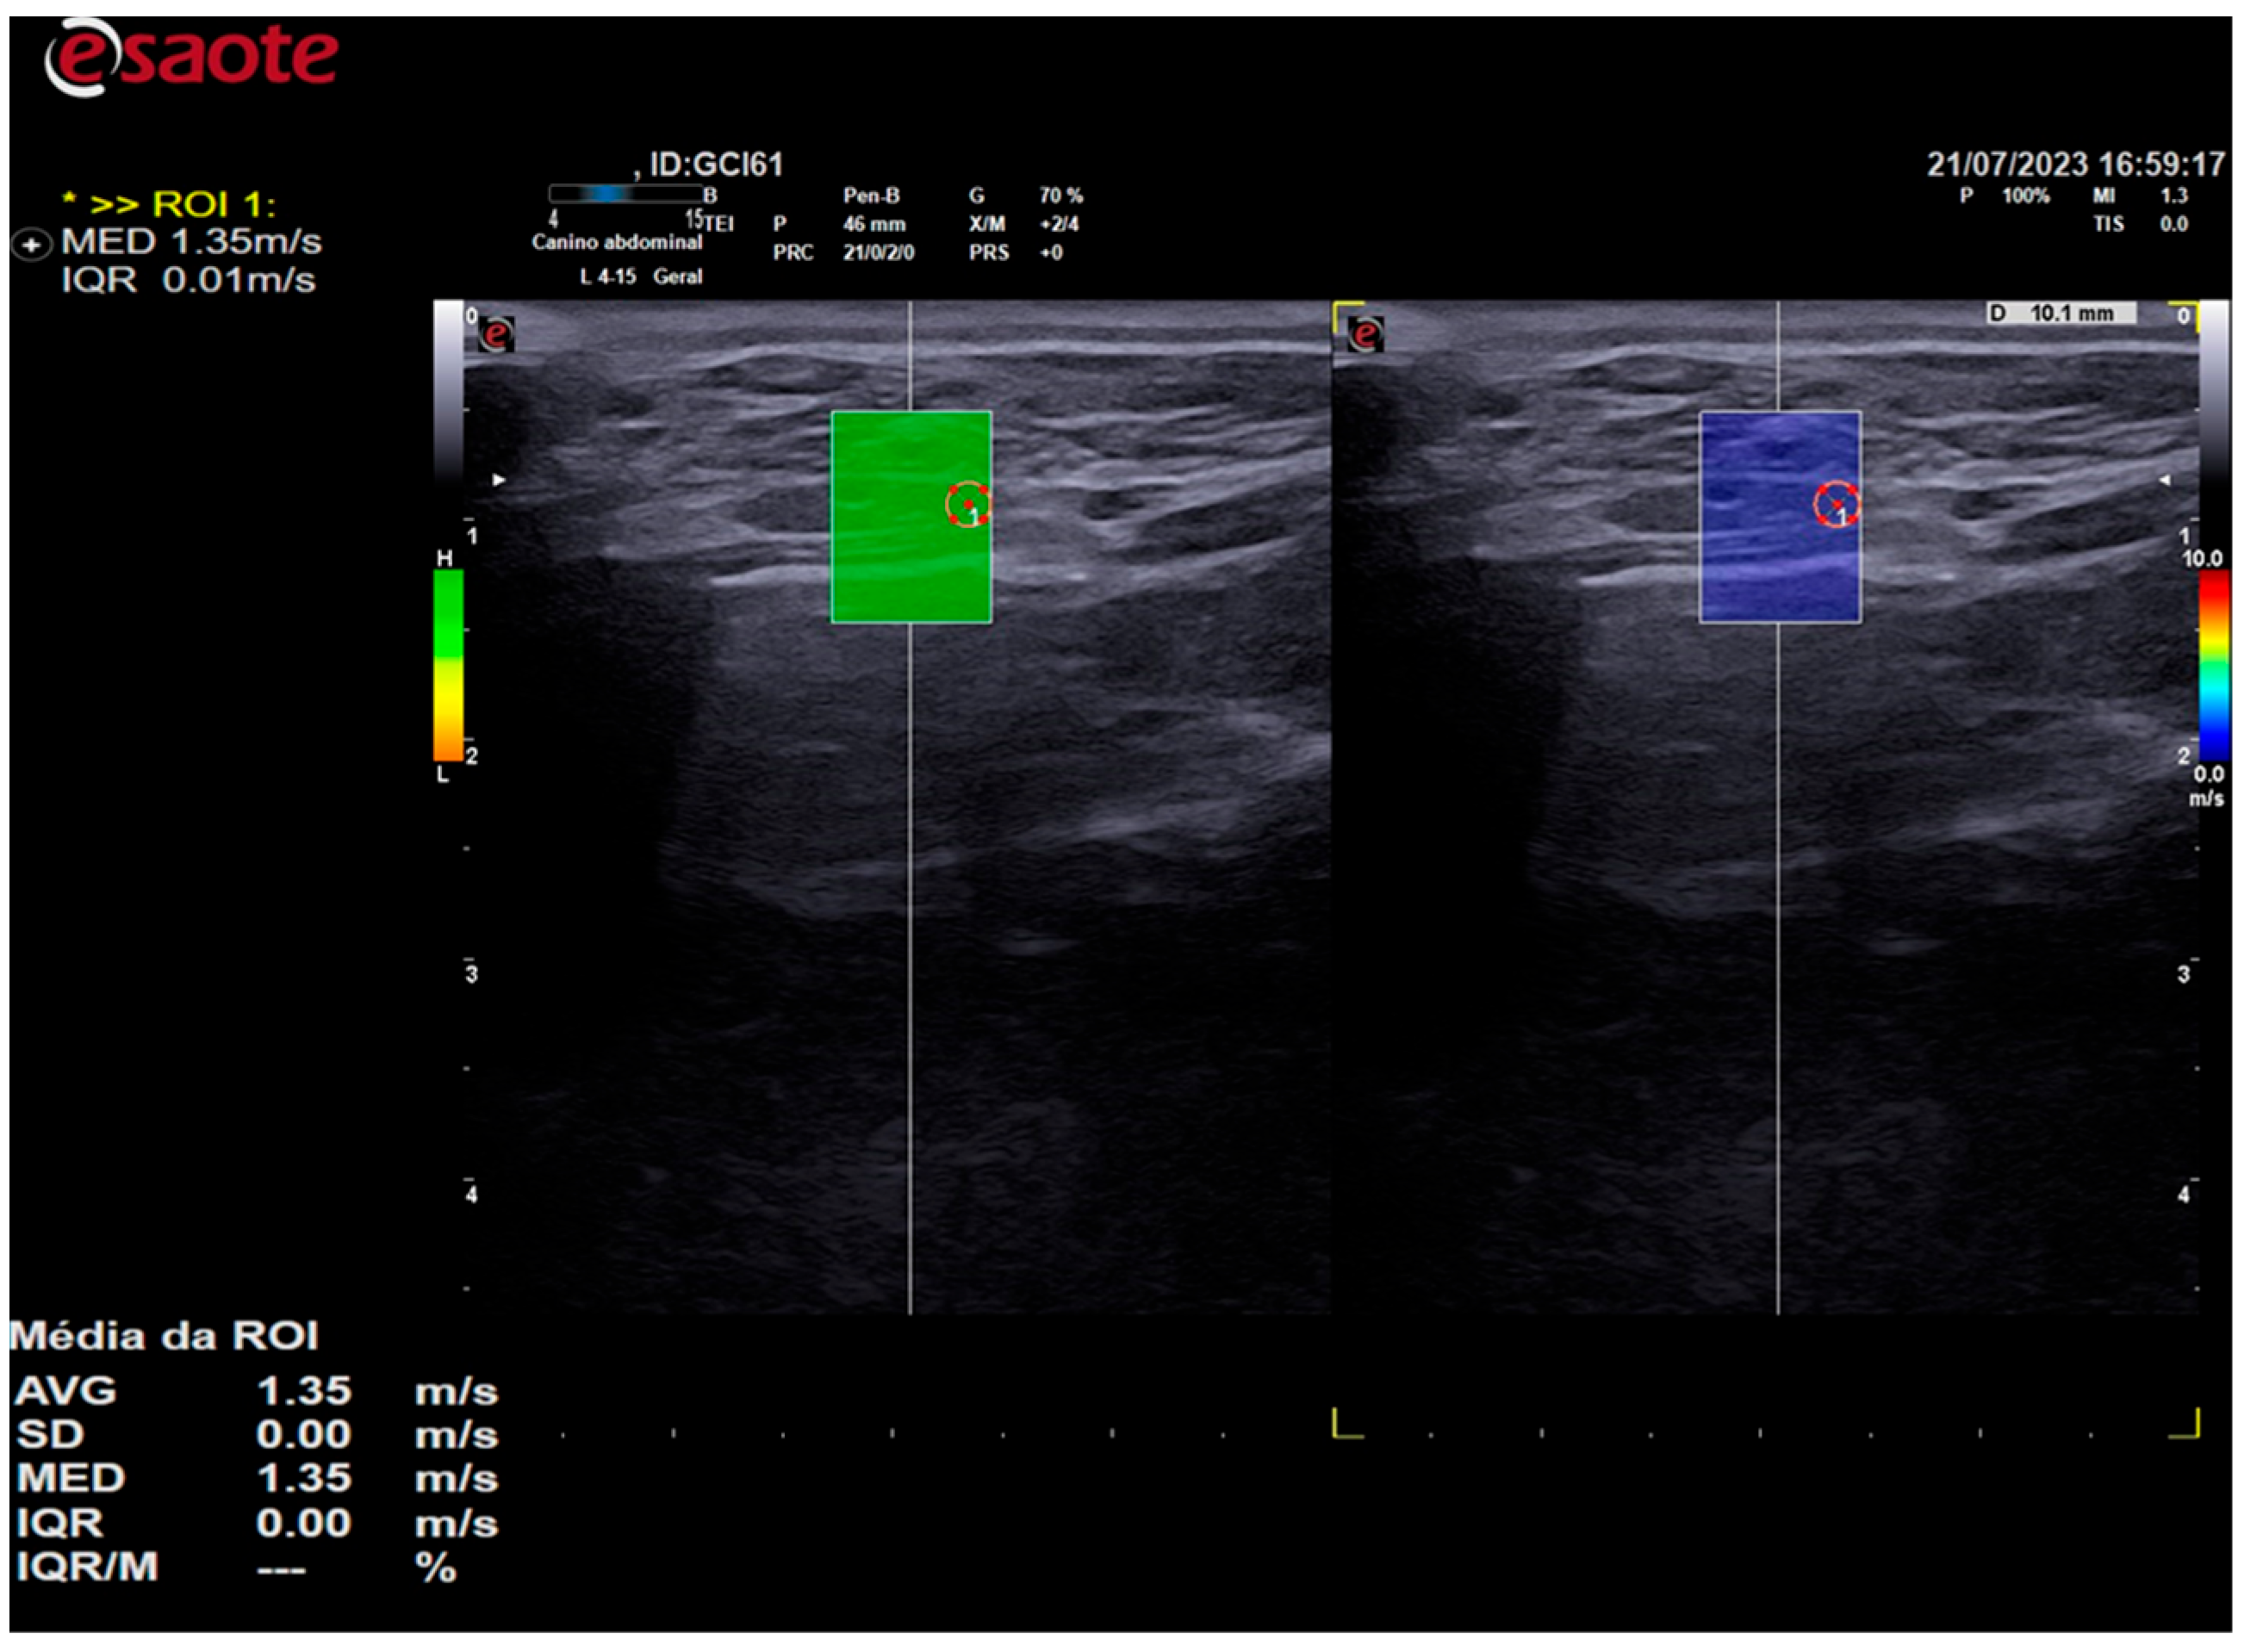

Elastographic images were obtained in the longitudinal plane of each thyroid lobe, and a scale of 0.0 to 10.0 m/s was employed in all cases. Once the thyroid lobe was properly framed in the image, the QelaXtoTM 2D software quality map was initiated. The map indicated the most suitable locations for acquiring shear-wave velocity. These were colored green to indicate high quality (Figure 3), yellow to indicate medium quality, and orange to indicate low quality (Figure 4).

Figure 4. The image on the left is a two-dimensional shear-wave elastography image of the left thyroid lobe of a 3-year-old female dog. The elastographic image on the left shows the quality map from the QelaXtoTM 2D software, which is colored orange. This indicates that the quality is low for measuring shear-wave velocity (quantitative). The right side of the elastographic image displays a colored elastogram (qualitative) from the QelaXtoTM 2D software, colored in blue, indicating that the thyroid parenchyma exhibited low stiffness (soft).